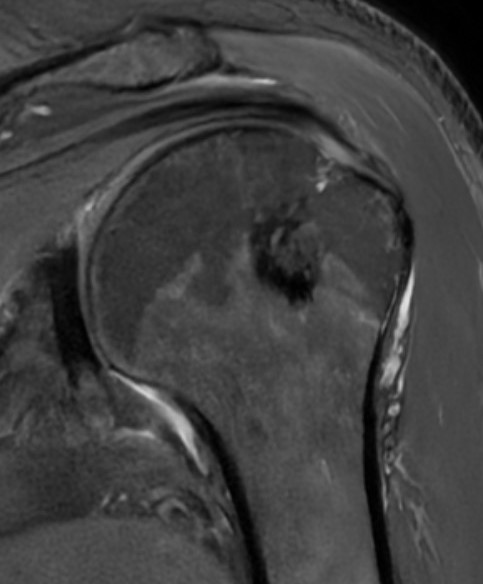

MRI

- Low signal on T1 and T2

- Do not enhance with contrast